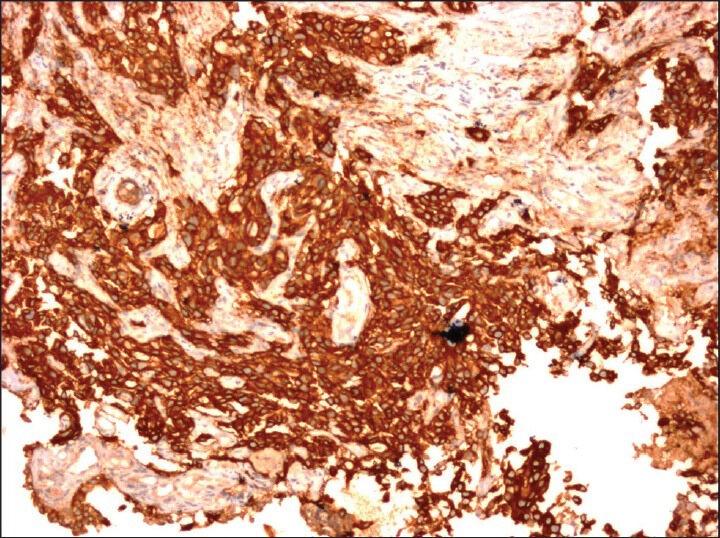

Lung cancer is a highly aggressive malignancy causing high morbidity and mortality. An increasing incidence of lung cancer has been observed in India. Currently, the classification of lung carcinoma has gone beyond small cell lung carcinoma and non-small cell lung carcinoma (NSCLC). Precise subtyping of poorly differentiated NSCLC into adenocarcinoma and squamous cell carcinoma has a direct impact on patient management and prognosis. With this background, many molecules are under study for developing targeted therapies. Epidermal growth factor receptor (EGFR) is one such biomarker considered to be useful in targeted therapy for adenocarcinoma.

The aim of this study was to subtype poorly differentiated NSCLC based on the expression of thyroid transcription factor-1 (TTF-1) and p-63 and to evaluate EGFR expression in adenocarcinomas.

A retrospective analysis of 84 cases of poorly differentiated carcinomas of the lung was performed. Paraffin sections were immunostained with TTF-1 and p-63 and the tumors were subtyped. EGFR expression was assessed in adenocarcinomas by immunohistochemistry.

Fifty-five percent of the NSCLC were adenocarcinoma, with a peak incidence between 61 and 70 years of age and a male predominance. EGFR was expressed in 89% of the adenocarcinomas.

Poorly differentiated non-small cell carcinoma can be subtyped by immunohistochemical markers and hence has a direct impact on the current therapeutic strategies.

肺癌是一种具有高度侵袭性的恶性肿瘤,导致高发病率和高死亡率。在印度,肺癌的发病率呈上升趋势。目前,肺癌的分类已超越小细胞肺癌和非小细胞肺癌(NSCLC)。将低分化NSCLC精确亚型化为腺癌和鳞状细胞癌对患者的治疗管理和预后有直接影响。在此背景下,许多分子正在研究用于开发靶向治疗。表皮生长因子受体(EGFR)就是这样一种被认为在腺癌靶向治疗中有用的生物标志物。

本研究的目的是基于甲状腺转录因子-1(TTF-1)和p-63的表达对低分化NSCLC进行亚型分类,并评估腺癌中EGFR的表达。

对84例低分化肺癌病例进行回顾性分析。石蜡切片用TTF-1和p-63进行免疫染色,并对肿瘤进行亚型分类。通过免疫组织化学评估腺癌中EGFR的表达。

55%的NSCLC为腺癌,发病高峰年龄在61至70岁之间,男性居多。89%的腺癌表达EGFR。

低分化非小细胞癌可通过免疫组织化学标志物进行亚型分类,因此对当前的治疗策略有直接影响。